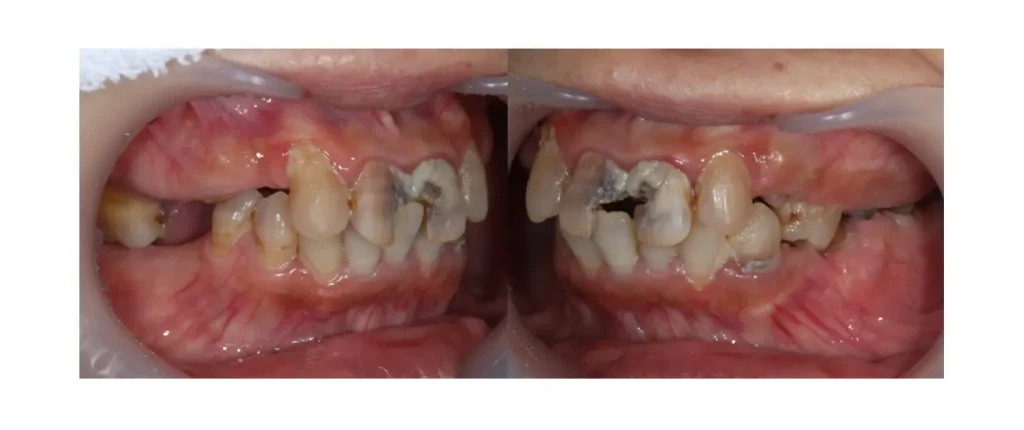

歯は隣同士で支え合っています。

歯が抜けると、隣の歯がそのスペースに向かって傾いて倒れてきます。

すると

- 歯並びの乱れ

- 噛み合わせのズレ

- 食べ物が詰まりやすくなる

といった問題が起こります。